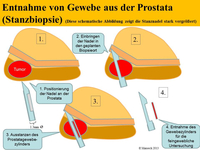

Im Allgemeinen spürt man den beginnenden Prostatakrebs nicht. Krankheitsspezifische Symptome werden erst in sehr späten Phasen der Erkrankung entwickelt. Um diese Symptome und die ernsthaften Folgen einer solchen Erkrankung zu verhindern, versucht man die Erkrankung frühzeitig zu diagnostizieren. Die wichtigsten diagnostischen Instrumente zum Nachweis eines Prostatakrebses sind die digital-rektale Untersuchung (DRU: Tastuntersuchung mit dem Zeigefingers des Arztes über den Enddarm), der PSA-Serumwert (ein Wert der durch eine einfache Blutabnahme ermittelt wird) und die transrektale Ultraschall-gesteuerte oder –gezielte Biopsie der Prostata.

Zunächst wird Ihnen der niedergelassene Urologe in der Region weiter helfen. Falls dieser den PSA-Wert für abklärungsbedürftig hält, wird er bei Ihnen ggf eine Probenentnahme der Prostata durchführen. Bringt eine solche erste, systematische Biopsie der Prostata keinen Tumornachweis und der PSA-Wert ist aber weiterhin auffällig bzw es gibt weiter Anlass für die Vermutung auf ein Prostatakarzinom, kann eine weiterführende Diagnostik mit innovativen, modernen bildgebenden Verfahren sinnvoll sein.

Die Methoden Ultraschall-Elastographie, der farbkodierte Doppler-Ultraschall sowie der kontrastmittelverstärkter Ultraschall und insbesondere die Echtzeit-MRT-Ultraschall-Fusion können helfen, auffällige Gebiete in der Prostata aufzuzeigen. So kann zum Beispiel ein in einer MRT (Magnetresonanztomographie) gefundener suspekter (also auffälliger) Bereich ganz gezielt biopsiert werden und auch zusätzlich noch elastographisch untersucht werden. Dies ist während einer herkömmlichen MRT-Untersuchung nicht möglich.

Eine multimodale Prostataabklärung erlaubt uns, die Prostata mittels modernster Verfahren zu untersuchen. Hierbei kommen verschiedene Untersuchungsmethoden zur Anwendung. Insbesondere die Echtzeitelastographie oder die kontrasmittelunterstützte Untersuchung der Prostata können hierbei wichtige Erkenntnisse über die Beschaffenheit der Prostata beisteuern. Auffällige Areale können in Echtzeit schmerzfrei mit lokaler Betäubung abgeklärt werden. Als Besonderheit können diese modernen Methoden auch mit einer bereits durchgeführten MRT-Untersuchung der Prostata fusioniert werden. Das bedeutet, in einer MRT gefundene auffälligen Areale der Prostata können zusätzlich mit modernsten Ultraschalluntersuchungen kombiniert untersucht werden und dann auch gezielt mittels gezielter Prostatabiopsie abgeklärt werden. Diese Untersuchung ist dann multimodal (zB Elastographie + konventionellem Ultraschall + MRT-Fusion).

Sie benötigen für die Probenennahme keine allgemeine Narkose. Bei der reinen Echtzeitelastographie benötigen sie keinerlei Art der Narkose. Da die Probenentnahme auch bei der MRT-Fusion und bei der Elastographie-gezielten Biopsie über den Enddarm (und nicht über den Damm) durchgeführt werden können, erlaubt eine haarfeine Nadel die vorherige Gabe von lokalen Narkosemittel eine ähnlich schmerzfreie Behandlung, wie sie ihnen der Zahnarzt bei einer Behandlung eines Zahnes gewährt. Das bedeutet: Sie selbst schlafen werden der Probenentnahme nicht, spüren jedoch keine Schmerzen.

Zunächst einmal werden die bereits durchgeführten und von Ihnen mitgebrachten MRT-Bilder (1,5T-3T, mit/ohne rektale Spule, DICOM-Format) in unser Gerät eingelesen. Anschließend werden die suspekten Areale und die Organgrenzen der Prostata in der MRT-Bildgebung markiert. Nun beginnt der praktische Teil: In angenehmer Seitenlage wird über einen modernen transrektalen Ultraschall die Prostata aufgesucht und anhand der Anatomie der Prostata mit dem MRT Bild fusioniert. Der Untersucher sieht nun auf der linken Seite des Flachbildschirmes des Ultraschallgerätes das Original-MRT-Bild mitsamt des Markierungen und auf der korrespondierenden rechten Seite die Live Ultraschallbilder in denen die Markierungen der MRT-Untersuchung zu sehen sind. Die auffälligen Areale können nun einer Elastographie oder einer Kontrastmittel-Untersuchung unterzogen werden um den Grad der Auffälligkeit zu bestimmen. Auf Wunsch können auch jetzt gleich die Biopsien durchgeführt werden.